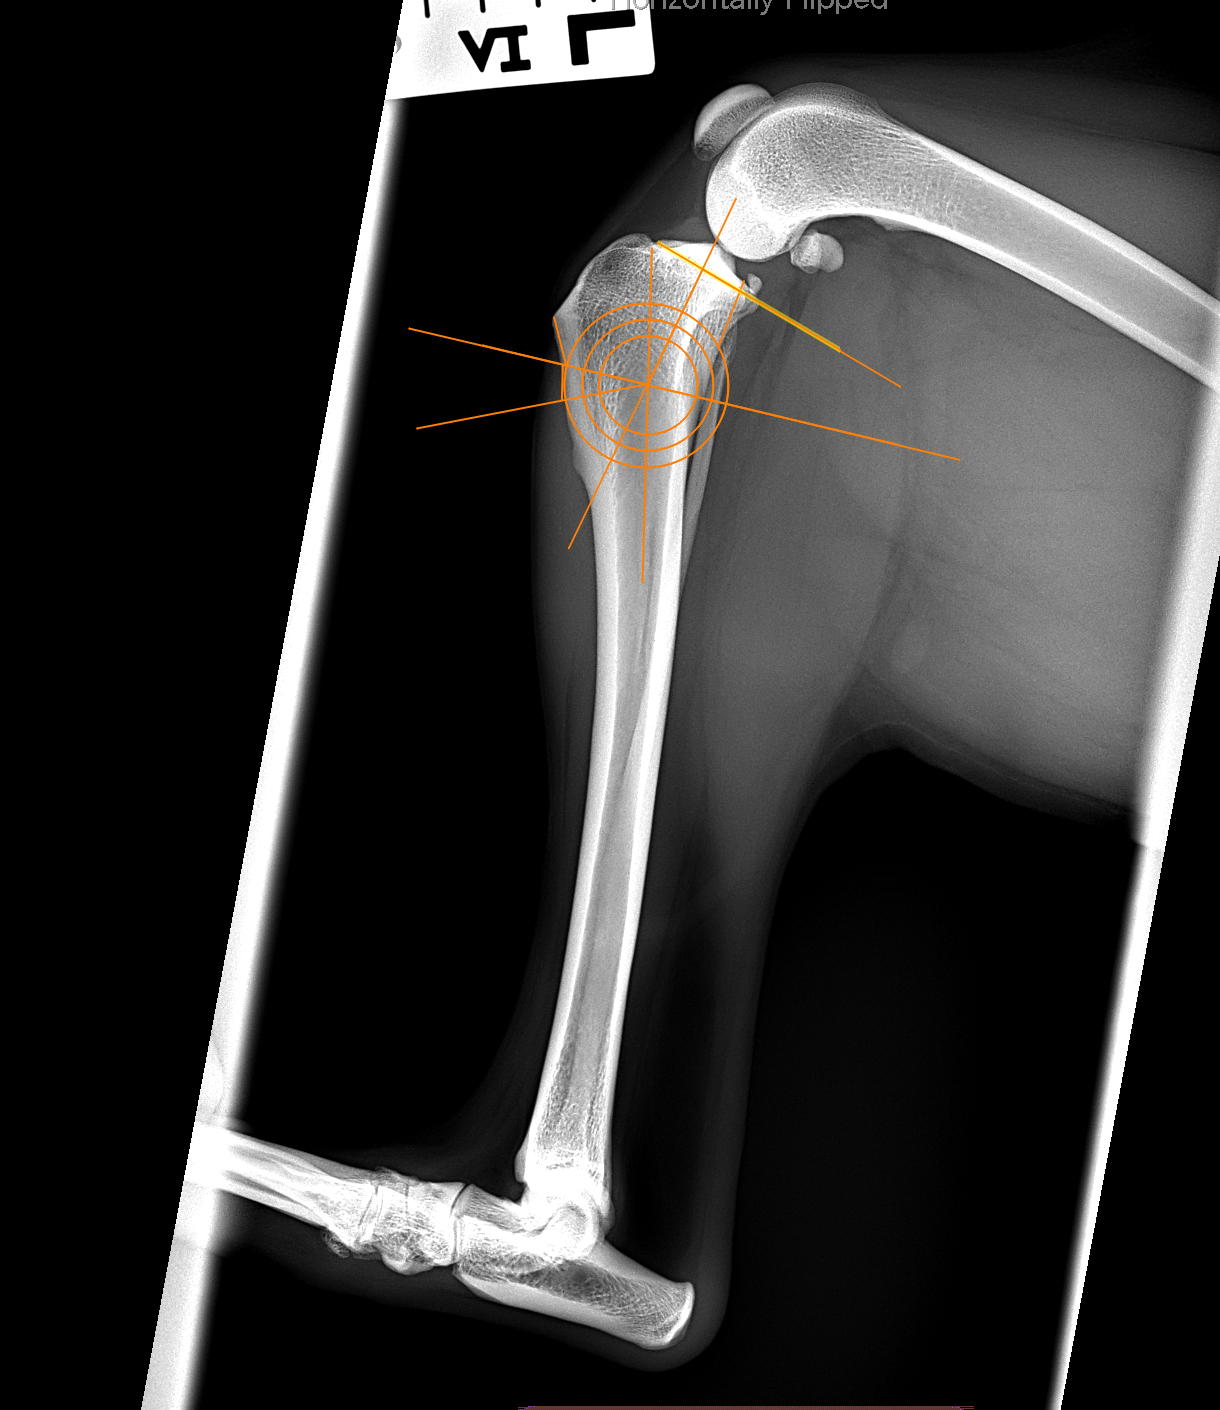

犬の前十字靭帯(疾患)部分断裂に対するCBLO #253

前十字靭帯部分断裂の患者さんに対して、CORA Based Leveling Osteotomyで対応しました。(2.7 Rita CCWO Plate+3.5 Locking Screw+4.0 Head Less Compression Screw) 。しばらく安静が必要です。